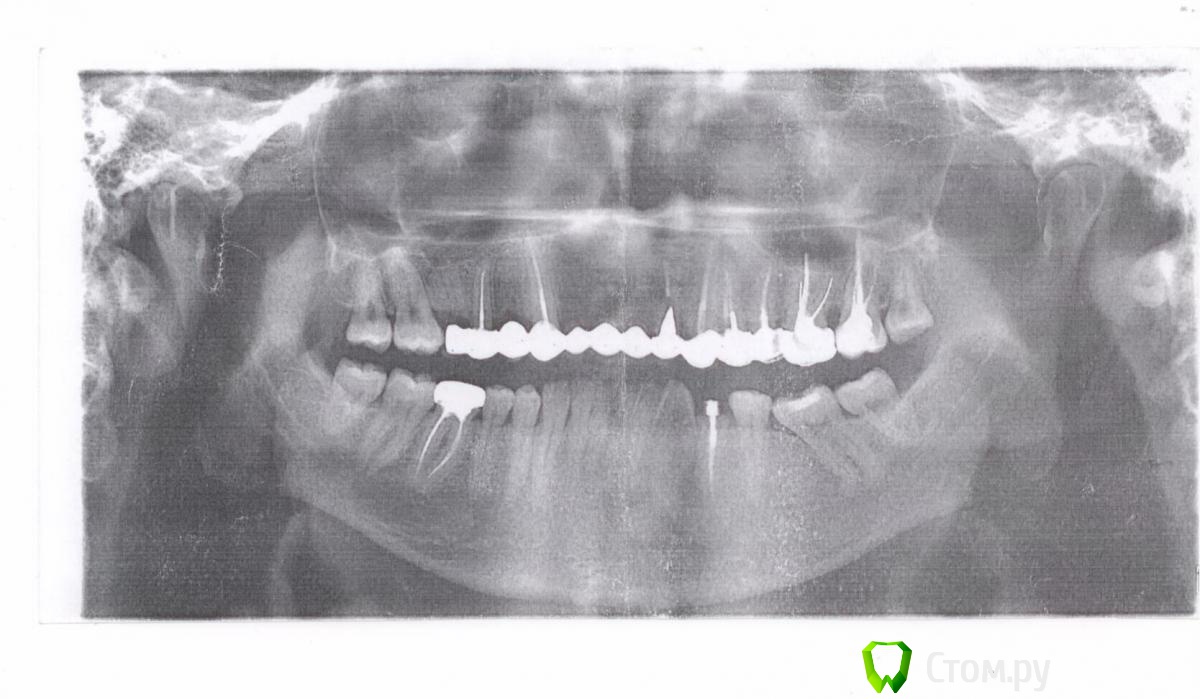

svp-mgdn Опубликовано 7 августа, 2014 Поделиться Опубликовано 7 августа, 2014 (изменено) Всем доброго времени суток! Ситуация следующая: так получилось, что еще в далеком юношестве я потерял все четыре верхних резца вместе с корнями. Плюс к этому на верхней челюсти были и другие "пробелы".В 2001 году в местной клинике был установлен длинный мостовидный протез на основе металлокерамики. Так как средств на имплантацию тогда не было, под местом верхних резцов образовалась пустота. Но, что интересно, данная конструкция прослужила верой и правдой до сего года, когда на правой единице образовался скол.Протез заканчивается на шестерках, слева и справа. Решение о замене протеза назревало уже давно в силу следующих причин:1. Линия верхних зубов. Так как в силу долгой по времени пустоты соседние зубы "поплыли" (я так это понимаю) протез поставили на то, что есть, особо не заморачиваясь. В итоге получился сильный скос вправо, что видно по фотографии (она зеркальна!).2. Эстетика. Цвет подбирали под нижние и, понятно, металлокерамика мало чем похожа на реальные зубы. Хотелось бы посветлее на тон как минимум, понатуральнее...3. Форма верхних резцов. Они получились какими-то каплевидными... Хочу прямоугольные, нормальные. Итак, планирую следующие работы в шесть этапов: 1. Единицы сверху слева и справа - импланты.2. После установки имплантов, установить временный протез.3. Протезирование верха: 1,2,3,4,5 сверху справа и слева - керамику на основе циркония ( титана?)4. 6й сверху справа (вместо существующего "подвесного") , 4й слева снизу ( там уже вывалился штифт, корень в плохом состоянии) , - импланты.5. Протезирование оставшихся. Снизу справа, 6ой - замена металлической коронки на керамику. В нашем городе все эти дела мне обойдутся около 200 тыс... Крайне дорого стоит протезирование. Но вживление конечно буду делать на месте.Поэтому хочу после имплантации и установки абатментов (правильно?) на верхние единицы ( либо сразу поставить все 4 импланта) протезироваться в Китае, в гос. клинике в Хэйхэ.Сейчас веду переписку с русским специалистом из этой клиники. Советует протезироваться титаном. Но насколько я знаю там многое зависит от марки сплава, чтобы не было ванадия...Но вот только не понятно, получится ли в плане эстетики так же как на основе циркония и смогут ли сделать ровную линию зубов? Это самое важное... Уважаемые, что могли бы посоветовать? Заранее большое спасибо! Изменено 7 августа, 2014 пользователем svp-mgdn Ссылка на комментарий